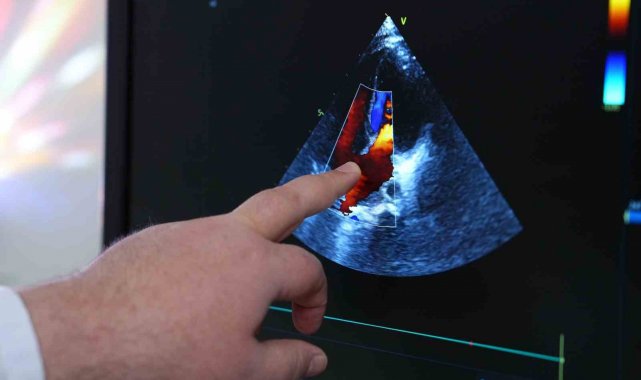

"Çocukların dünyasında gözden kaçan hipertansiyon, sinsi bir düşman. Çoğu zaman belirti vermeden ilerleyen ve bu nedenle çok geç fark edilen bu sağlık sorunu, küçük kalpler için büyük risk taşıyor. Türkiye'de maalesef çocukların tansiyon ölçümleri yeterince yapılmıyor" açıklaması yapan MedipolMega Üniversite Hastanesi Çocuk Kardiyolojisi Uzmanı Prof. Dr. Cenap Zeybek, özellikle kardiyolojiye yolu düşmemiş evlatlarda yüksek tansiyonun belirlenmesinin geciktiğini aktarıyor. Zira, yetişkinlerle kıyaslandığında hem nedenleri hem de tedavi yolları farklılık gösteren çocukluk çağı hipertansiyonunun mutlaka ciddiye alınması gerektiğini ifade eden Prof. Dr. Zeybek, konunun önemine dikkat çekiyor.

Hipertansiyonun çocukluk çağında genellikle geç fark edildiğini dile getiren Prof. Dr. Zeybek, "Ülkemizde çocuklarda rutin tansiyon ölçme alışkanlığı bulunmuyor. Bu nedenle özellikle kardiyoloji takibi olmayan çocuklarda hipertansiyon kolay kolay fark edilmiyor. Ancak ergenlik döneminde ölçümlerle birlikte tanı konulabiliyor" dedi. Çocuklarda hipertansiyonun erişkinlere kıyasla daha çok yapısal nedenlere dayandığını vurgulayan Prof. Dr. Zeybek, "Erişkinlerde obezite, diyabet, sigara gibi faktörler öne çıkarken, çocuklarda böbrek, böbrek üstü bezi, kalp ve endokrin sistemle ilgili problemler hipertansiyona neden olabiliyor. Bu nedenle tanı ve tedavi daha kapsamlı bir yaklaşım gerektiriyor" diye konuştu.

Çocuklarda kan basıncı değerlendirmesinin yaşa, kiloya ve boyuta göre farklılık gösterdiğini belirten Prof. Dr. Zeybek, "Erişkinde 140/90mmHg'nin üzeri hipertansiyon sayılırken, çocuklarda her yaş grubuna özel tansiyon aralıkları var. Bu yüzden her yaşa özel değerlendirme yapılmalı. Çocuk endokrinolojisi, çocuk nefrolojisi, kardiyoloji, diyetisyen gibi farklı branşların ortak takibiyle hipertansiyon kontrol altına alınabiliyor. Öncelikle altta yatan nedenin tespit edilip o nedene yönelik tedavi planlanmalı" dedi.